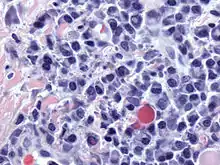

Micrograph of malignant plasma cells (plasmacytoma), many displaying characteristic "clockface nuclei", also seen in normal plasma cells. H&E stain. | |

Plasma cells are large lymphocytes with abundant cytoplasm and a characteristic appearance on light microscopy. They have basophilic cytoplasm and an eccentric nucleus with heterochromatin in a characteristic cartwheel or clock face arrangement. Their cytoplasm also contains a pale zone that on electron microscopy contains an extensive Golgi apparatus and centrioles (EM picture). Abundant rough endoplasmic reticulum combined with a well-developed Golgi apparatus makes plasma cells well-suited for secreting immunoglobulins.[2] Other organelles in a plasma cell include ribosomes, lysosomes, mitochondria, and the plasma membrane.

Plasmacytoma, multiple myeloma, Waldenström macroglobulinemia and plasma cell leukemia are malignant neoplasms ("cancer") of the plasma cells.[13] Multiple myeloma is frequently identified because malignant plasma cells continue producing an antibody, which can be detected as a paraprotein.